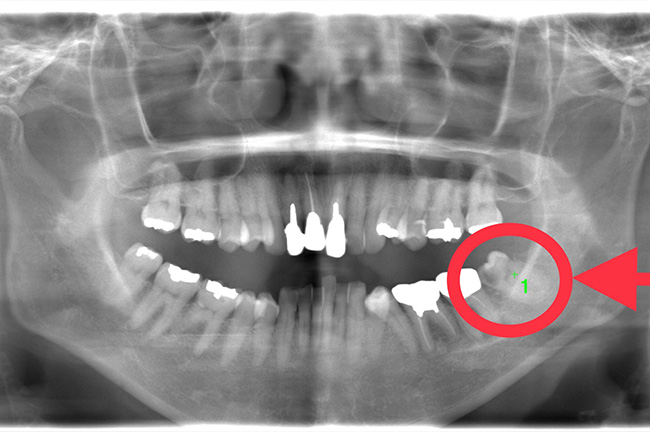

CASE 11

親知らずは真っ直ぐに生えていましたが一部歯ぐきが被っており、歯ブラシが上手くできず虫歯になり歯石もたくさん付いていました。

術中・術後痛み出血もほとんどなく、抜歯後は親知らずを抜いた事により歯磨きが楽になったと喜ばれていました。

治療前パノラマ

途中経過

抜歯後

基本情報

| 年齢・性別 | 40代・男性 |

|---|---|

| 主訴 | 親知らずが磨きにくいので抜きたい |

| 治療内容 | 右下親知らず通常抜歯 |

| 治療期間 | 約30分 |

| 治療費 | 合計約6,000円 約2,500円(保険診療3割負担) 別途CT撮影で約3,500円 (2022年12月現在) |

| リスク・副作用 | 下顎の歯は、骨の中を通っている血管、神経や舌の神経に近接しているため、術後に下唇や舌の知覚異常を起こす可能性があります。 |

| 治療方針 | 事前にCT撮影を行い神経との位置関係を確認して抜歯を行いました。 |